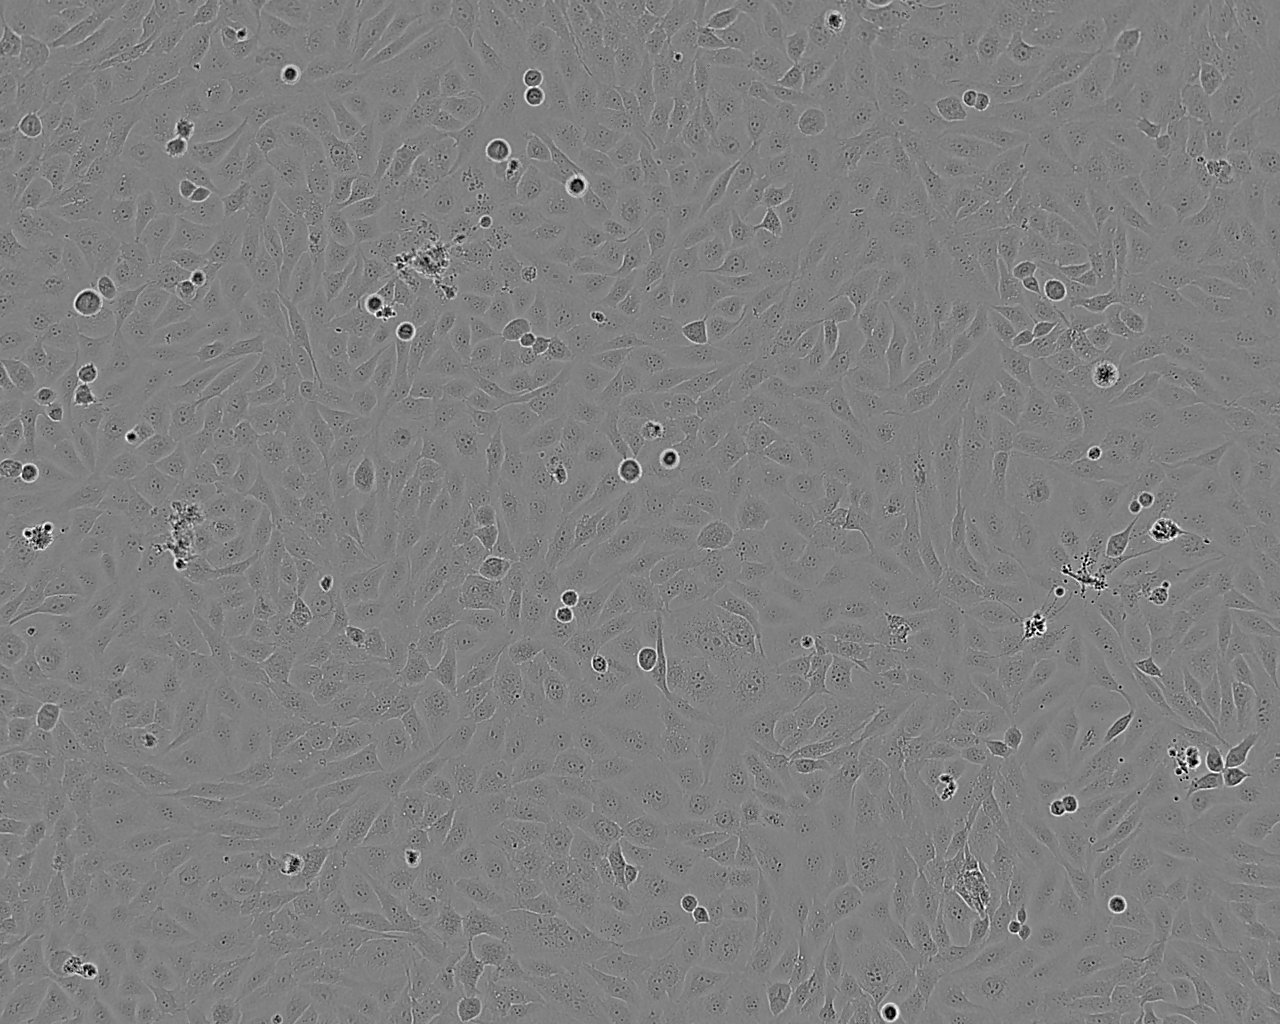

细胞形态:上皮细胞样

细胞生长:贴壁

细胞生长特性:贴壁

细胞形态特性:详见细胞说明书